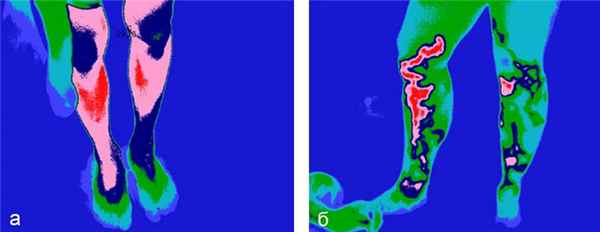

Возможна также диагностика различных заболеваний брюшной полости, особенно грыж [22]. Диагноз острого аппендицита ставят в основном по клиническим симптомам. Термография как объективный метод клинической визуализации может служить дополнением к диагностическому процессу, особенно в неясных клинических случаях, избавляя больного от инвазивных методов диагностики (рис. 2) [23].

Рис. 2. Термографическая диагностика острого аппендицита: a — норма; б — острый аппендицит